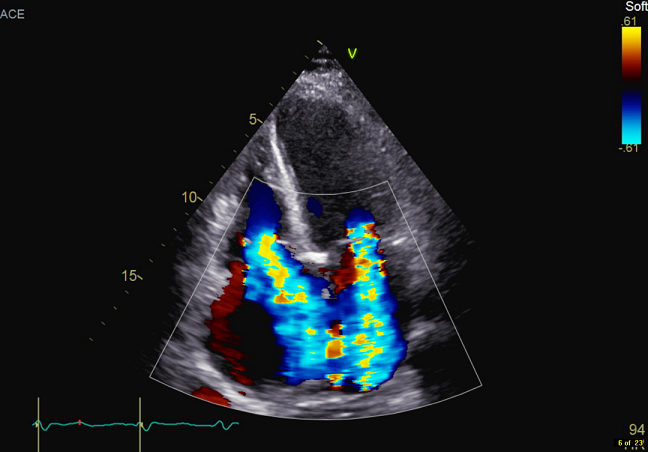

经过一段时间的对症治疗,患者症状有所缓解,但复查结果显示二尖瓣及三尖瓣仍为重度关闭不全,经心外科团队共同探讨,患者具备外科手术指征,决定在全麻体外循环下行二尖瓣置换术、三尖瓣成形术、左心耳缝合术 。术后患者恢复良好,现已治愈出院。

术后彩超影像